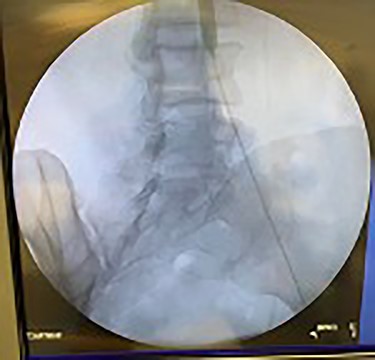

Catheter arteriogram results showed significant occlusion of the left iliac artery (Figs 3 and 4), the right iliac artery (Fig. 1), as well as the distal abdominal aorta (Fig. 2). There were numerous collateral vessels noted, indicating the presence of long-standing proximal stenosis (Fig. 1). The decision was made to use angioplasty to help widen the areas of stenosis. An 8 mm × 40 mm Passeo balloon was advanced from the right femoral artery into the left iliac artery (Fig. 7) and insufflated to 6 mmHg (Fig. 6). The balloon was allowed to remain expanded for 1 min and then was deflated. Next, the distal aorta was repaired in a similar fashion. The balloon was advanced into the distal aorta from the right femoral access and insufflated to 12 mmHg (Fig. 8). The balloon was allowed to remain expanded for 90 s.

Fluoroscopy of right iliac artery showing vast collateral vascular formation, indicating long-standing proximal obstruction.